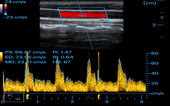

Carotid

MSK

MSK